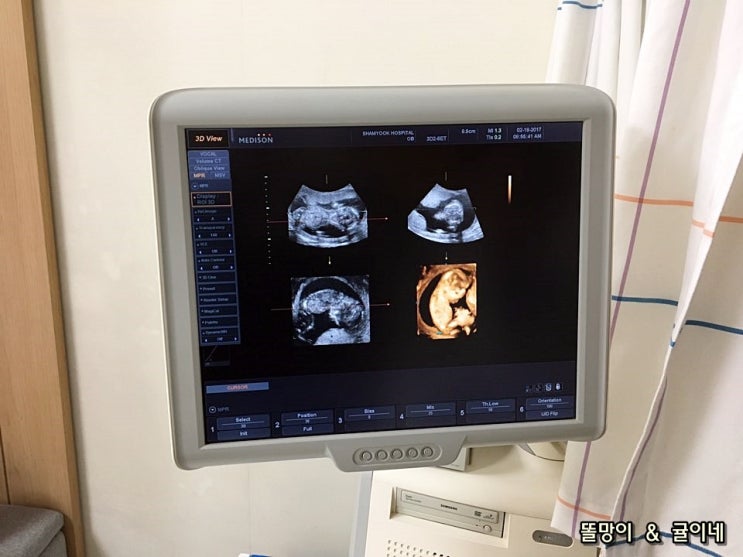

* 임신 17주 * 기형아검사,귤이 성별확인

안녕하세요~ 똘망이맘이에요:) 이제 임신 중반기에 접어들면서 병원가는 횟수도 띄엄띄엄 가게 되네요. 17...